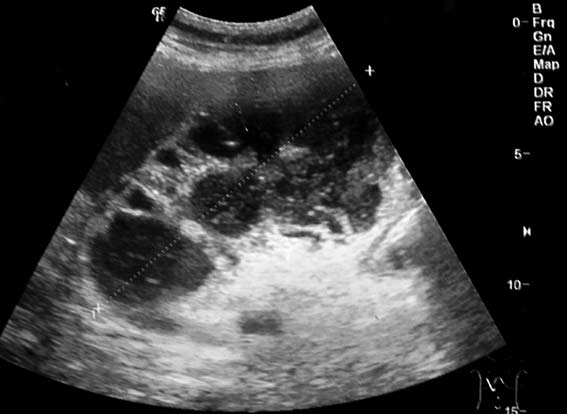

Пожилой мужчина, с высокой температурой и болями в правом подреберье. Болен более недели.

Острый холецистит, подпеченочный абсцесс

ЖП увеличен в размерах, стенка утолщена и на всем протяжении не прослеживается, содержимое неоднородное, но конкрементов я не вижу... Эмпиема ЖП - возможно, острый гангренозный холецистит (нельзя исключить на фоне карциномы ЖП) На снимке вокруг ЖП определяется гипоэхогенное образование без четких границ- перфорированный ЖП (гнойный перихолецистит ???)

В действительности на сонограмме подпеченочный абсцесс вследствие гангренозного воспаления желчного пузыря. Сам пузырь плохо дифференцируется в этом конгломерате.